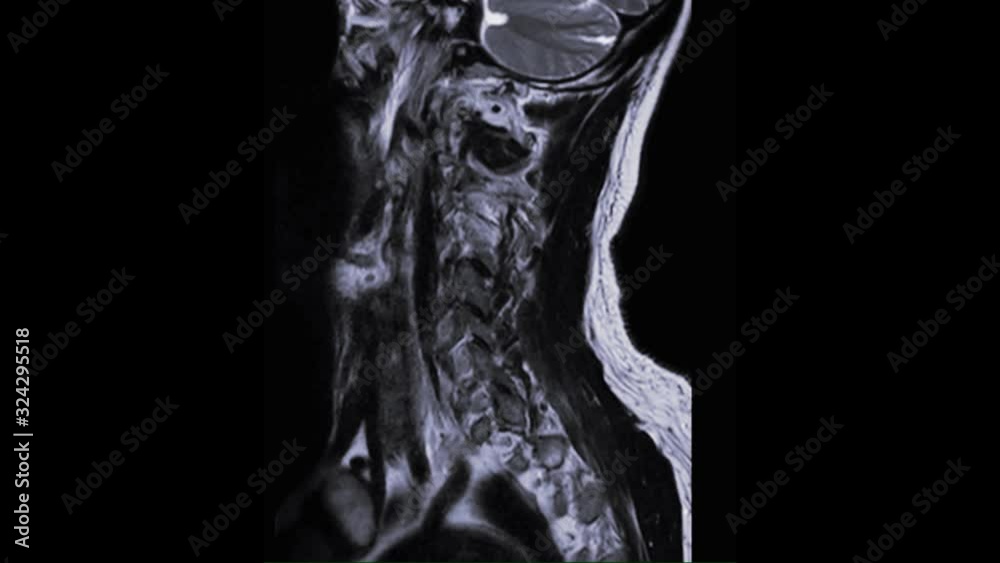

MRI of cervical spine sagittal T2W view for diagnostic Spinal Cord Spinal Cord Compression At C3-4 Symptoms of cervical myelopathy may include problems with fine motor skills, pain or. This article will focus on atraumatic causes of spinal cord compression, including degenerative. Treatment is directed at relieving compression. Various lesions can compress the spinal cord, causing segmental sensory, motor, reflex, and sphincter deficits. Spinal cord compression—also called cervical spondylotic myelopathy (csm)— is caused by any condition. Spinal Cord Compression At C3-4.

From stock.adobe.com